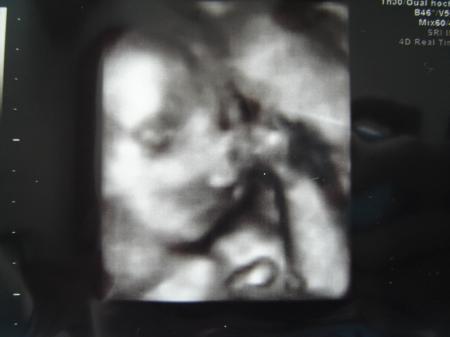

Alles ist in Ordnung. Blutverdünner darf ich absetzen und mein Gebärmutterpuls hat sich regeneriert. Der kleine Prinz ist zeitgemäß entwickelt und wiegt 704g. Hat ihm gar nicht gefallen, dieses kalte Gel und der Schallkopf auf meinem Bauch...hat ganz schön gestrampelt und dagegen geboxt! Sein Herzchen ist auch in Ordnung und hat keine Auffälligkeiten. Ach bin ich froh... Ich bin nur etwas erstaunt über meine Plazenta! Laut meiner FA hab ich eine Vorderwandplazenta, jetzt steht im Bericht Hinterwand. Kann sich sowas in der SS ändern?

So ein süßes Bild von deinem Kleinen! Schön, dass sonst alles gut ist. Das mit der Plazenta ist schon komisch, wie sollte die denn von vorne nach hinten gewandert sein? Vielleicht hatte der Arzt sich beim ersten mal verguckt? LG Mechthild